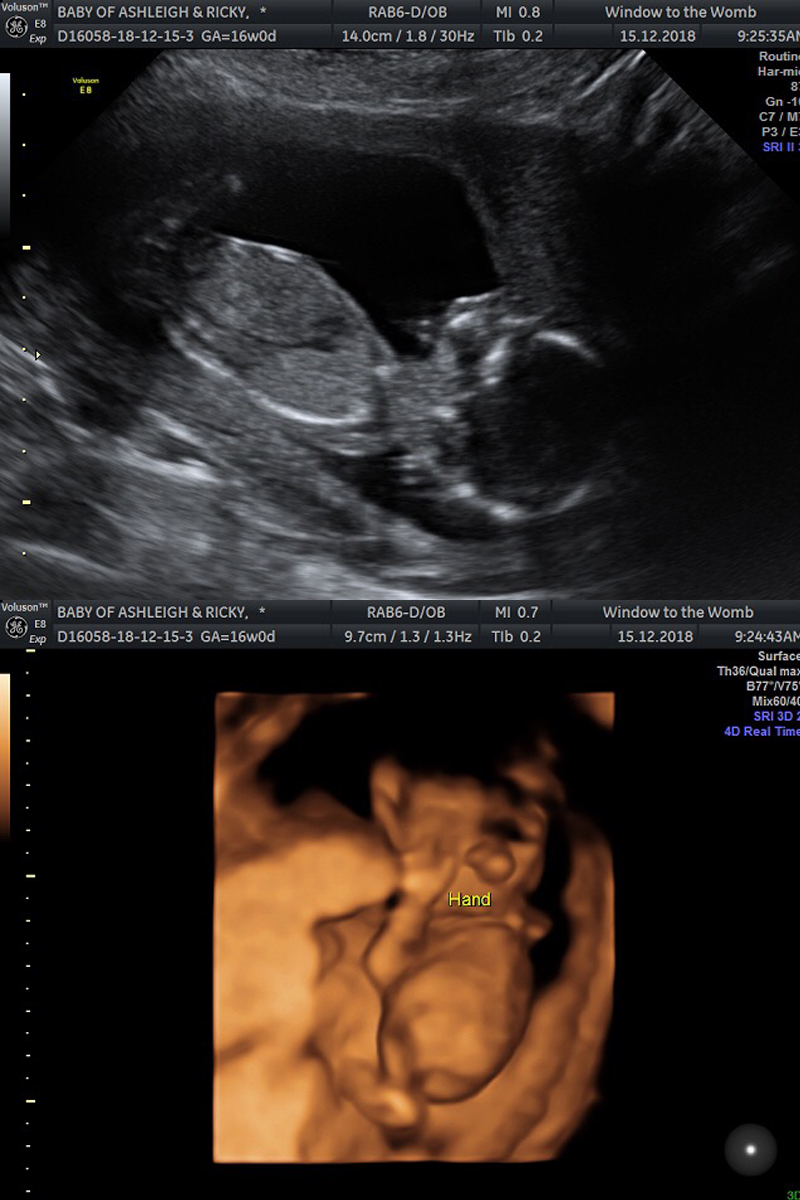

Onto the scan itself incase anyone is interested in reading more about early gender scans. We had ours at 16 weeks.

I cannot recommend Window To The Womb private clinics enough (*not sponsored). You are made to feel welcome and special the moment you walk in and the scan itself is made to be much more special in my opinion. We had the same sonographer as our early 6 week scan, so it was nice to see a familiar face and the setting is super comfortable and relaxing; spa like music and low, warm lighting and a sofa provided for up to 5 guests that you are allowed to bring.

The package we paid for gave us a gender reveal, health check and a sneak preview in 4D - something we was all really looking forward to.

Baby is a little wriggler and kept moving around, mostly standing on this head! However, these two photos are my favourite as you can really see details. In the 4D photo, it sort of looks like a huge nose, but it's actually his two hands on his face. You can see a thumb so clearly!